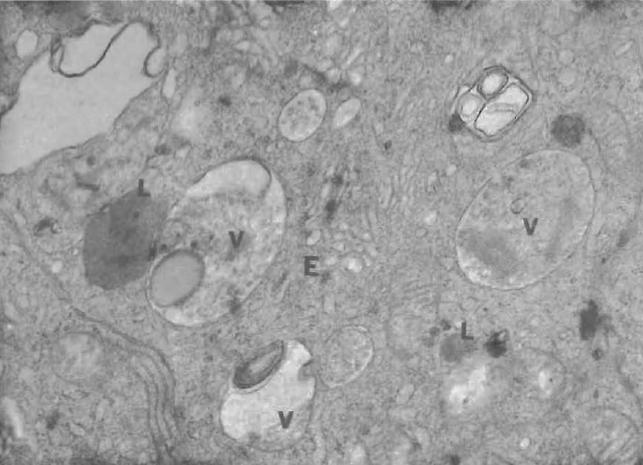

Light and electron microscope studies of the effects of gossypol acetic acid, a phenolic compound isolated from cotton plants, on epididymal tissue in DBA/2J mice were undertaken since the information on the effects of the compound on the male reproductive tract in mice is limited. The agent, mixed in olive oil, was administered orally to four groups of mice and upon the sacrifice, the epididymal tissues were dissected and prepared for light and electron microscopy. Administration of the drug substantially reduced sperm motility and viable sperm counts and induced anomalies in sperm heads, sperm parts, and mitochondrial structures. Numerous vesicular structures containing granules and concentric membranous bodies in the principal and light cells, dilation of the Golgi complex and endoplasmic reticulum, and a cumulation of lysosomal bodies were found in epididymal cells. The severity and frequency of the ultrastructural changes increased with the dose and duration of the treatments.